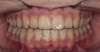

Dans ce but, un fil de contention est collé sur la face interne des dents de l’arcade mandibulaire (du bas), de canine à canine.

Cette même contention est assurée à l’arcade du haut par le port d’une gouttière nocturne (dispositif en plastique moulé sur l’arcade idéale du patient obtenue en fin de traitement). On peut aussi, dans certaines situations, coller un fil de contention à l’arrière des dents du haut.